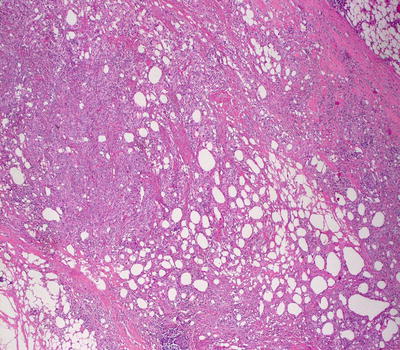

9.3.2 Histology

Biopsy of subcutaneous fat necrosis of the newborn demonstrates a lobular panniculitis [19] (Fig. 9.5). There is a diffuse, brisk mixed inflammatory infiltrate within fat lobules. Necrosis of adipocytes results in crystal formation and small granulomas surrounding the degenerating cells [20] (Figs. 9.6 and 9.7). Crystals are needle-shaped, and can be present within degenerating adipocytes and histiocytes [21, 22]. Eosinophilic granules , a manifestation of degenerating eosinophils within the surrounding infiltrate, have been observed in some cases [23–25]. Dystrophic calcification is seen in late cases [20, 26, 27]. Radially oriented needle-like crystals are helpful in establishing the diagnosis on fine needle aspiration cytology [28, 29].

Fig. 9.5

Subcutaneous fat necrosis of the newborn is a lobular panniculitis that is characterized by a predominantly histiocytic response